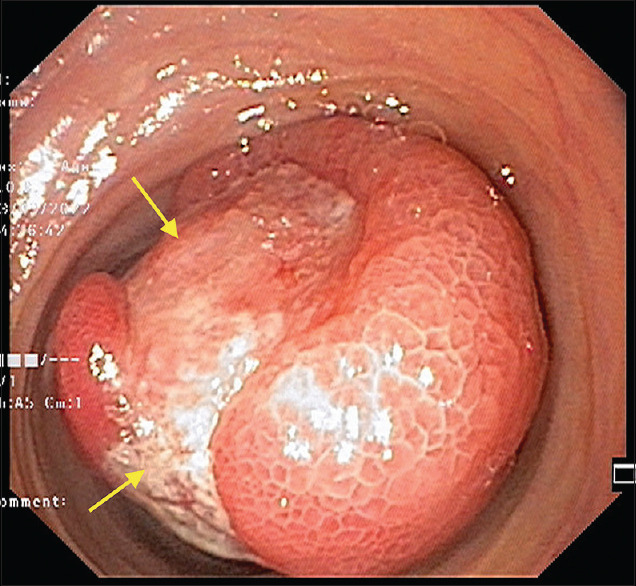

Abstract: Small bowel lipomas are benign submucosal neoplasm composed mainly of mature adipose tissue. Despite their rare occurrence, lipomas are the second most common benign tumour of the small intestine. These tumours are mostly small in size and remain clinically asymptomatic. However, larger lesions tend to be more symptomatic, presenting with complications such as intussusception, bleeding or obstruction. Definitive surgical or endoscopic intervention is indicated in such symptomatic lipomas. Herein, we describe a rare case of ileal lipoma presenting with ileo-ileal intussusception and a life-threatening haemorrhage that was managed by laparoscopic-assisted ileal resection.

Abstract Image